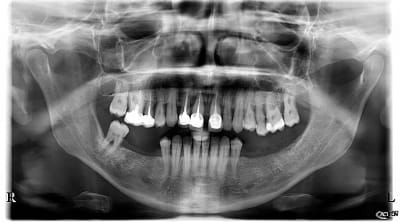

Patiente de 52 ans avec parodontite avancée

mon plan de ttt est le suivant extraction les dents aboluments non conservable (11-21-25) et tenter de garder le reste, puis réévaluer le cas apres surfacage et gingivectomie. Puis de couronner le reste: bridge 13 12 (11 21) 23, couronnes jumélées 14 15 16 17, bridge 24 (25) 26 27.

Ou extraction totale haut, implantation immédiate et mise en charge immédiate (j'adresserai a un implanto pour cela)

Pour le bas ca me parait plus simple, soins 47, surafacage, implant 46 45 35 36 + cr

Ta pano Acteon : c'est une X Mind One ou déjà une X Mind Trium ?

c'est la trium CBCT...

La pano c'est effectivement la xmind trium de acteon